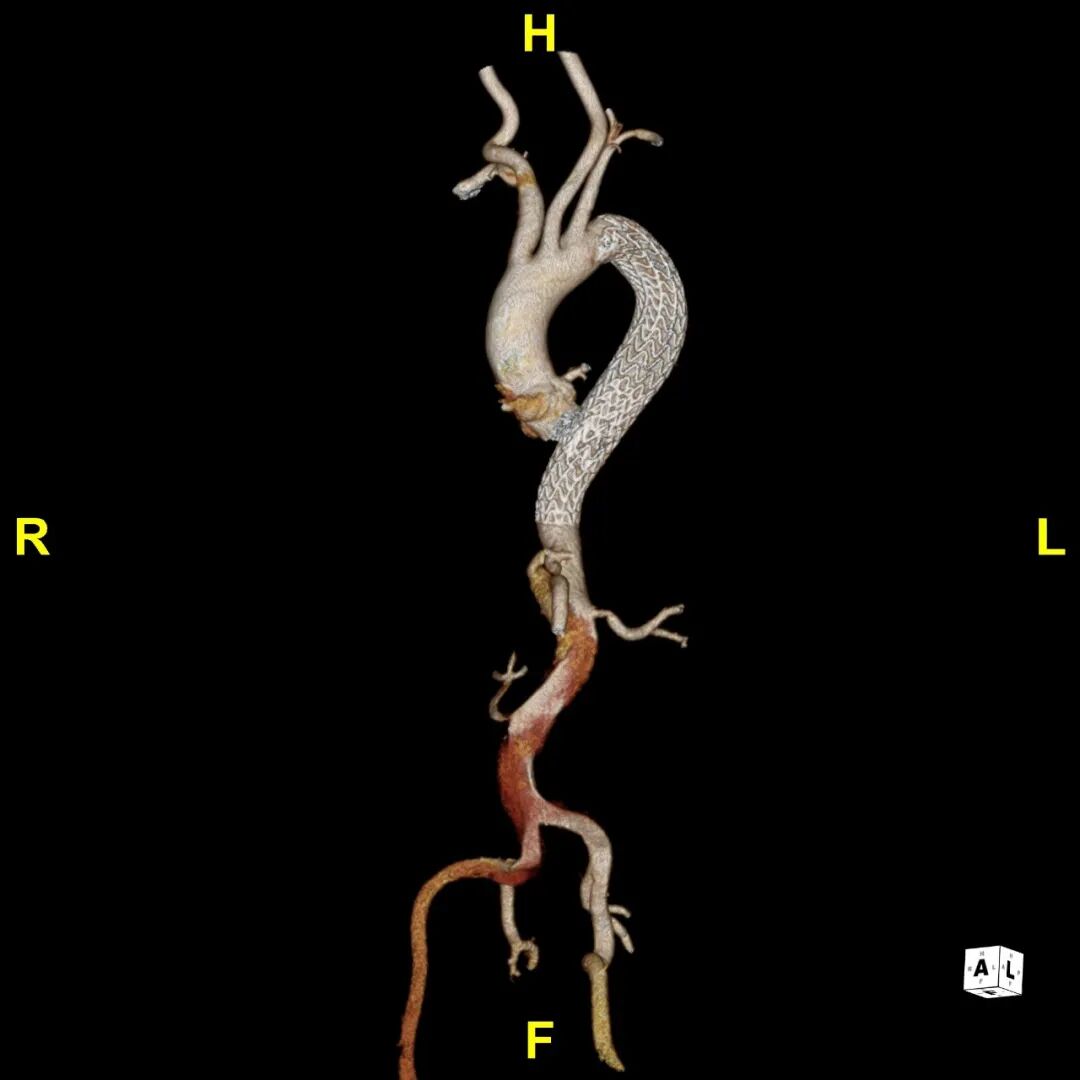

CTA提示患者主动脉弓型为Ⅲ型弓,左侧椎动脉为优势动脉,夹层累及至双侧髂外动脉,腹腔干动脉,肠系膜上动脉及左肾动脉为真腔供血,右肾动脉为真假腔供血,左侧胸腔少量积液。

术前3D重建动态

患者出院前进行CTA复查,支架形态良好,与血管壁紧密贴合无内漏,胸主段假腔隔绝,真腔重塑良好。

术后3D重建动态

术后3D重建